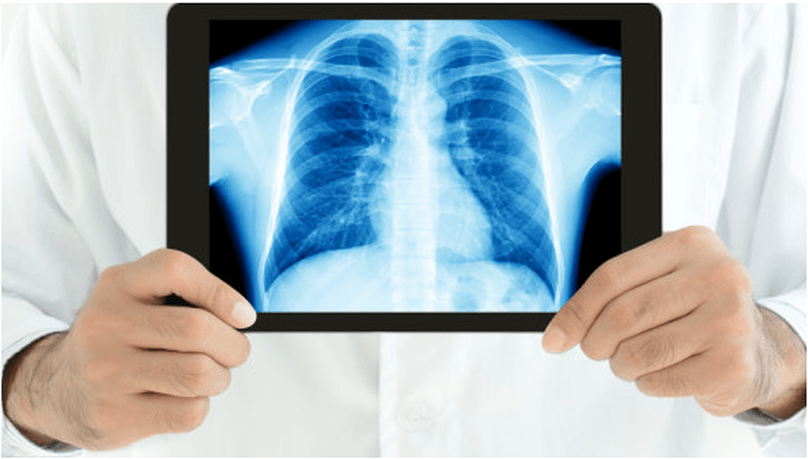

Digital X-ray, also known as computed radiography (CR) or digital radiography (DR), is an advanced imaging technology that has largely replaced traditional film-based X-ray systems.